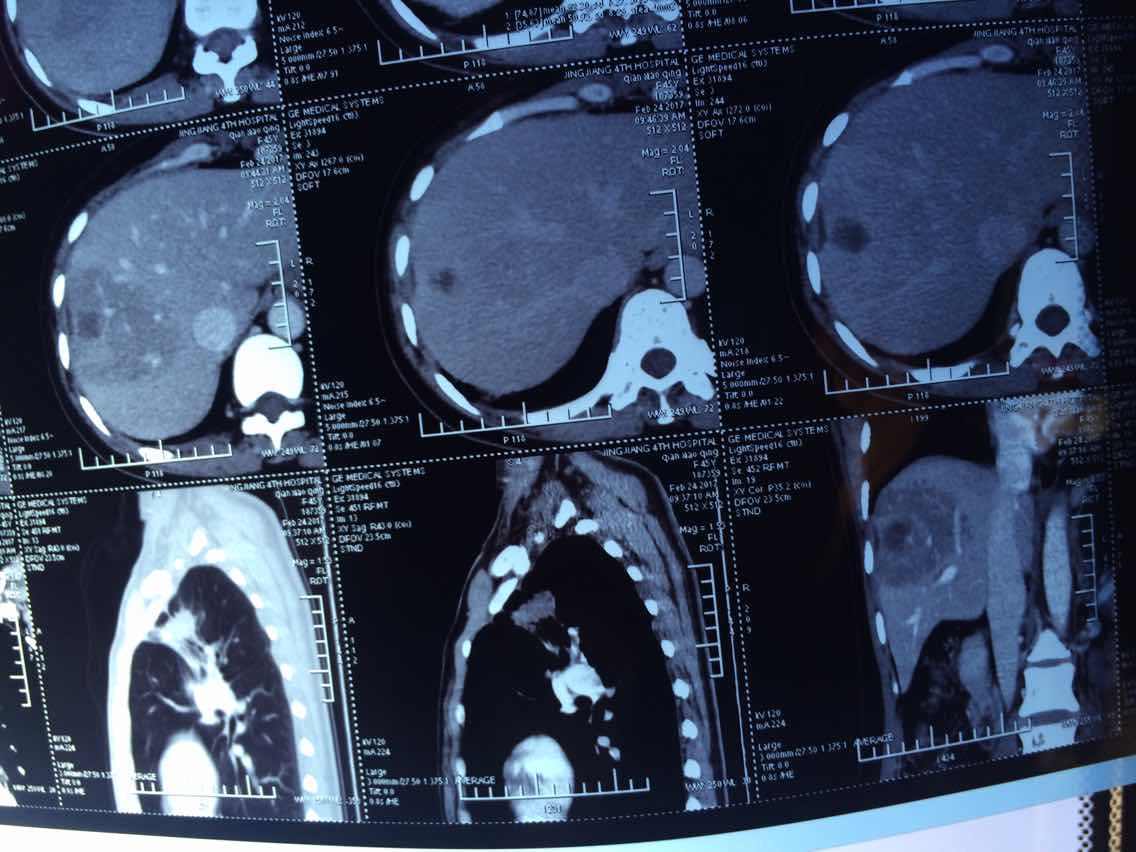

2017.10.29

举报

2017-10-31 10:44:24 有用(0)

回复(0)

2

2017-10-31 10:44:42 有用(0)

3

2017-10-31 10:45:01 有用(0)

4